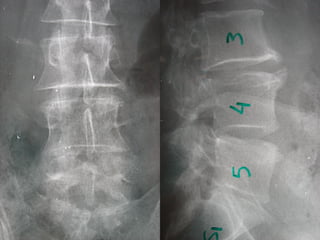

Imaging studiesImaging studies

Plain radiographs occasionally demonstrate

osteomyelitis but are of almost no utility.

Plain radiographsPlain radiographs